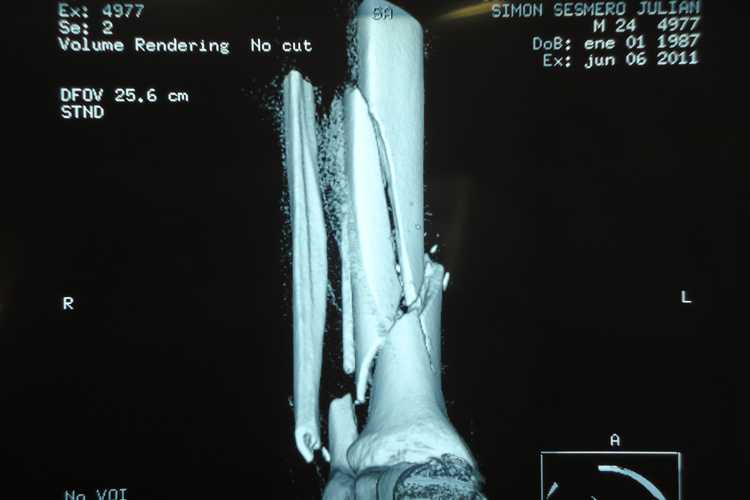

Bereits am Montag unterzog sich der Mapfre-Aspar-Pilot dem dreistündigen Eingriff. Gestern stellte sich heraus, dass die Operationswunde keine Probleme verursachen sollte, nun kann der Suter-Fahrer mit Physiotherapie beginnen. Die OP war aufwändig, weil die Rekonstruktion der zum Teil in sehr kleine Fragmente zersplitterten Knochen komplex war. Nun halten zwei Platten, die mit mehreren Schrauben im Schien- und Wadenbein verankert wurden, die gebrochenen Knochen zusammen.